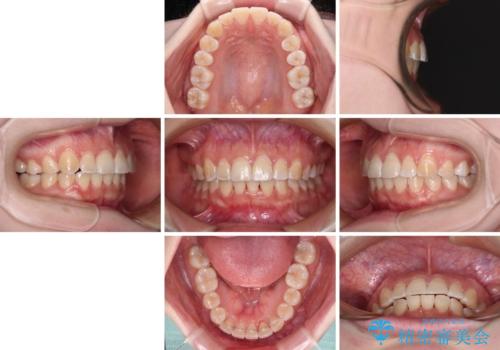

患者様も驚く、僅か10か月での治療終了となりました。

下顎前歯が1歯欠損しているため、上下正中は合わず、左右奥歯の咬み合わせは理想的とはならない仕上がりとなります。